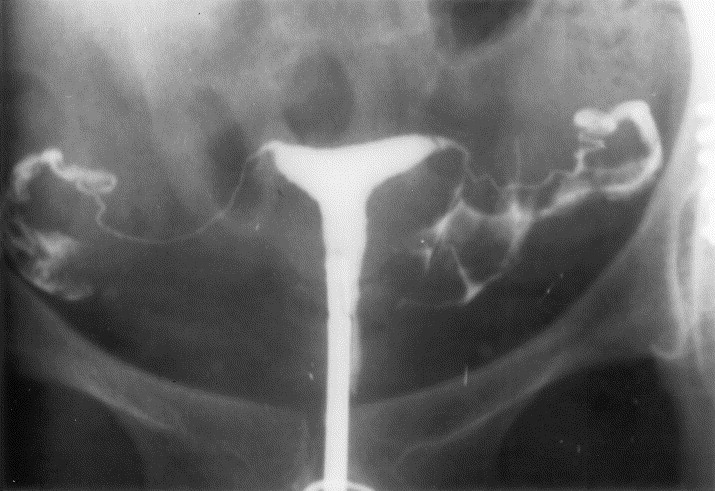

산과력 0-0-0-0인 32세 여성이 임신을 원하나 임신이 되지 않아 병원을 찾았다. 부부는 지난 2년 동안 임신을 시도해왔으나 성공하지 못했다고 한다. 여성의 최종월경시작일 4일차에 시행한 혈액검사, 배우자(남편)의 정액검사 결과와 자궁난관조영술 결과이다. 임신을 위한 적절한 처치는?

• 혈중 호르몬 농도와 HSG 소견이 정상이므로 ovulatory dysfunction, uterine factor, tubal factor 등의 가능성은 낮다.